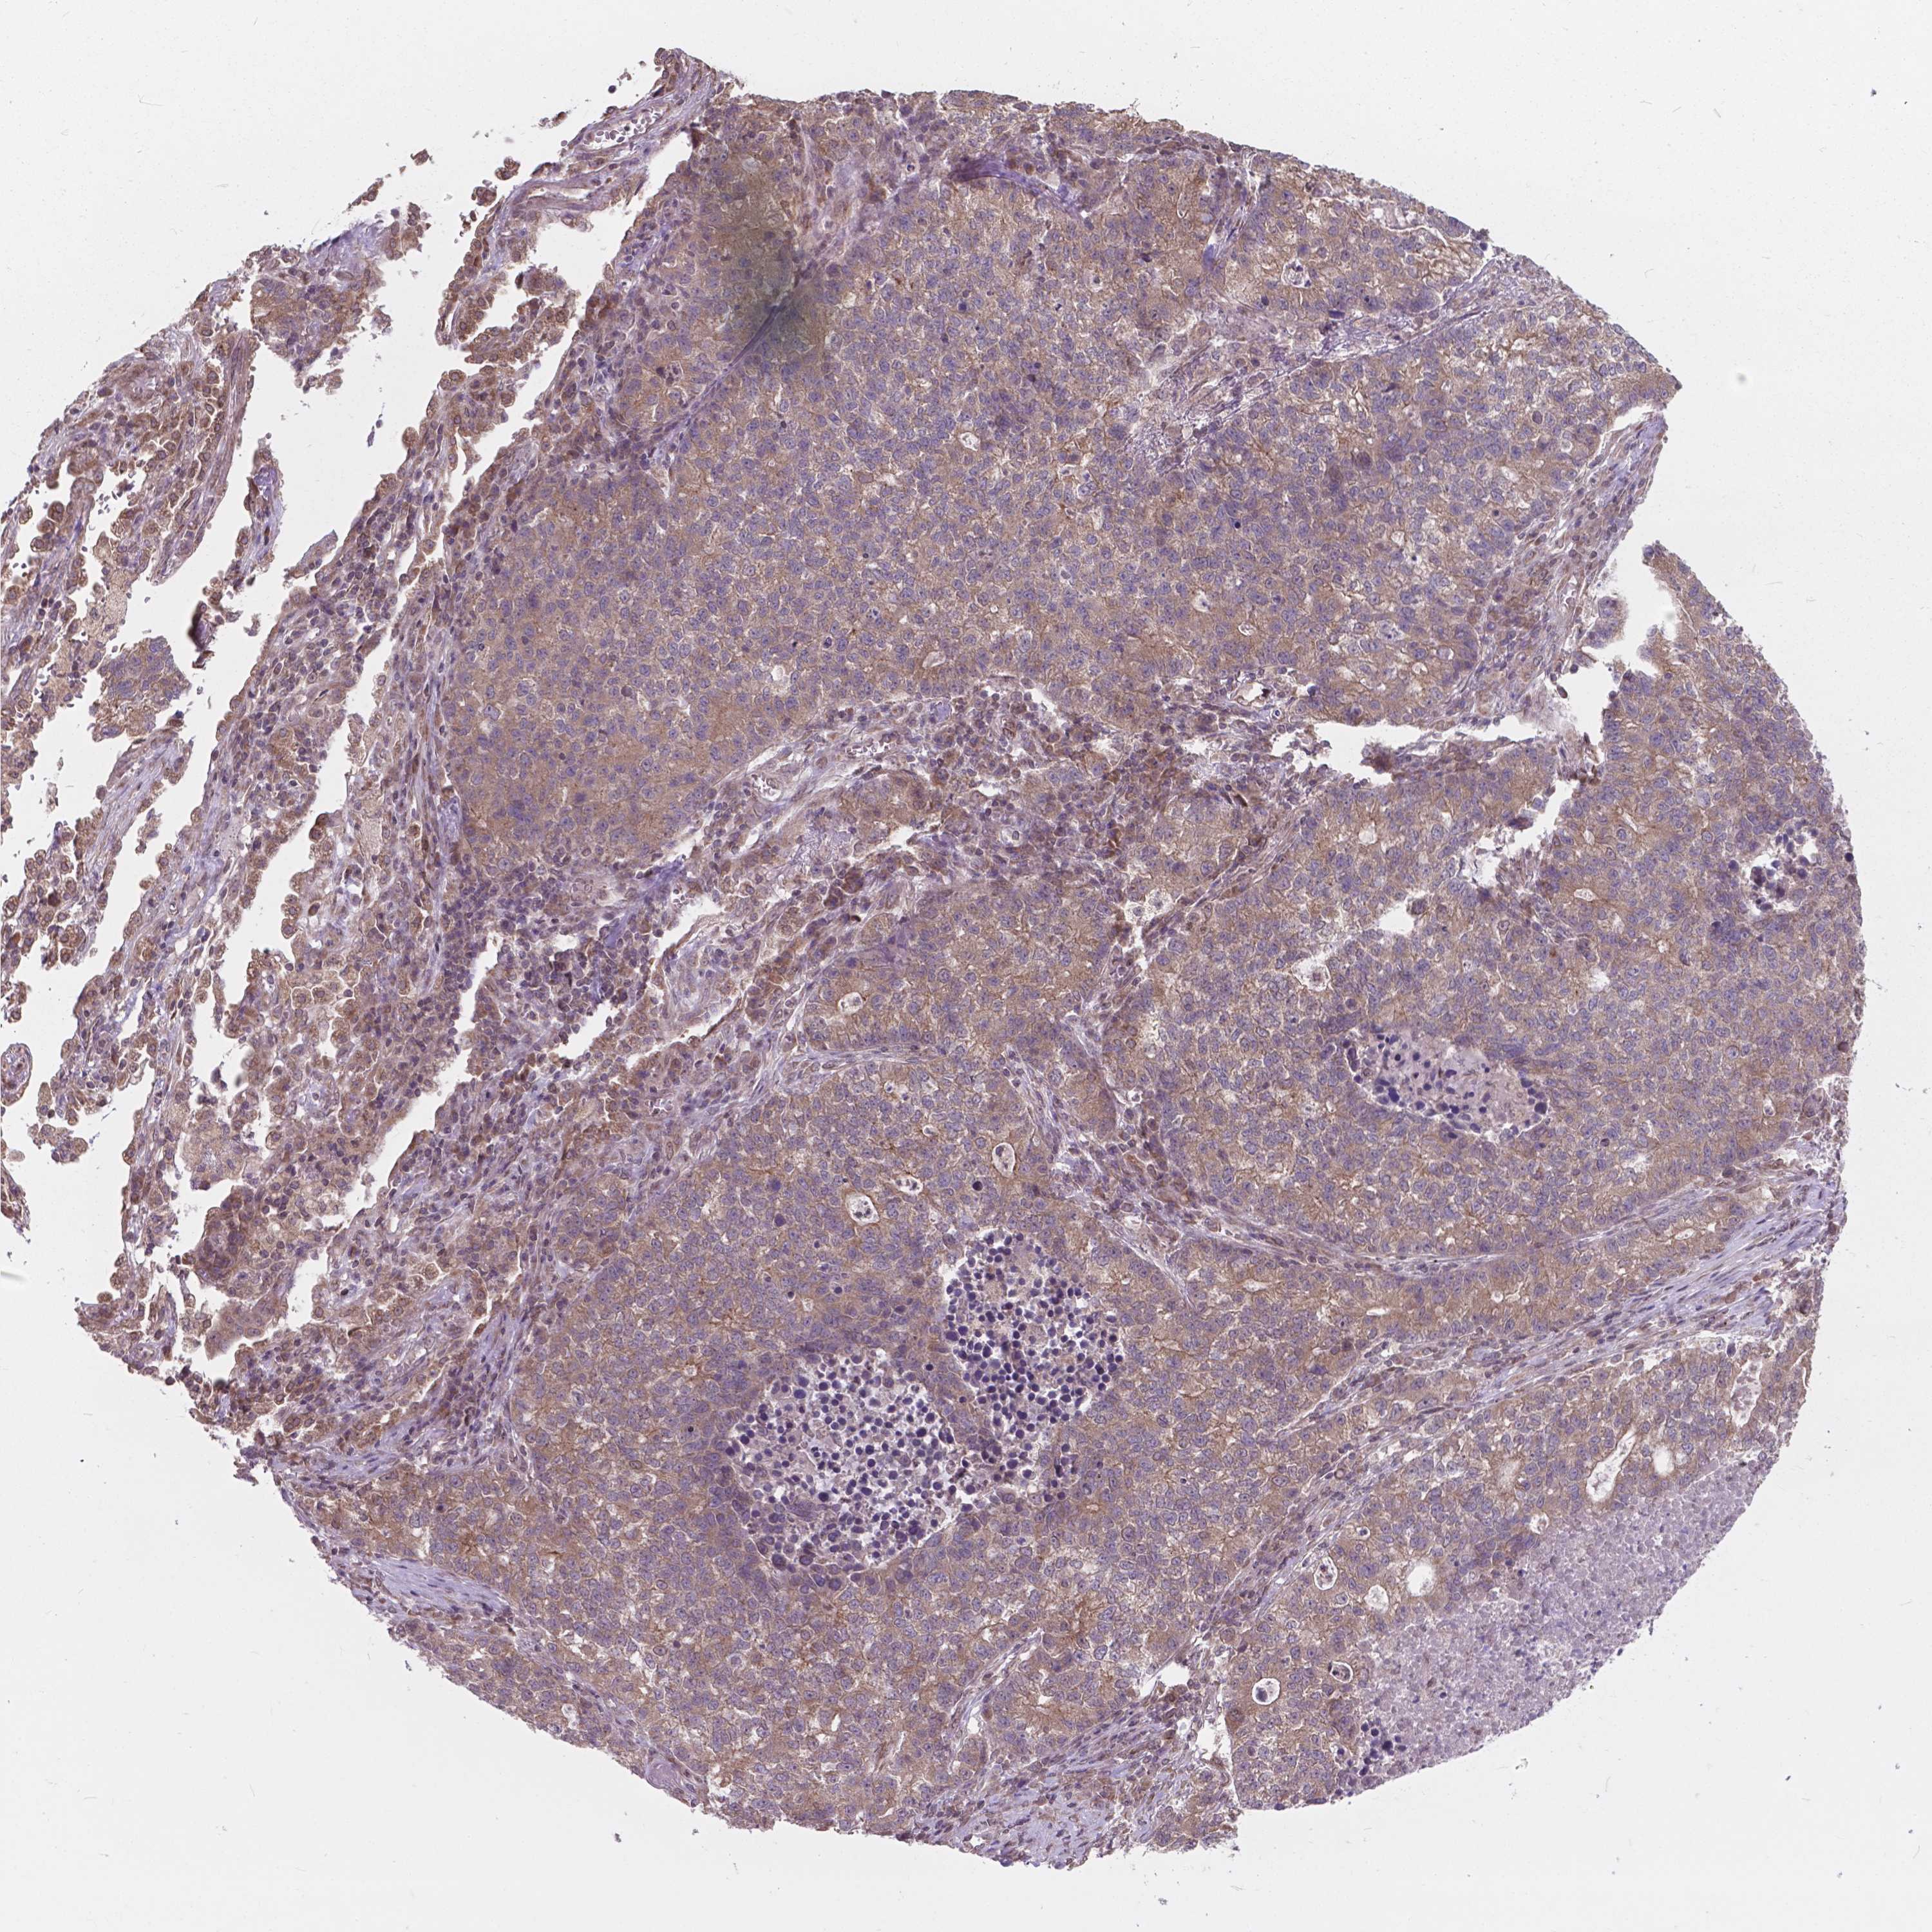

LUNG ADENOCARCINOMA (VALIDATION) - Interactive survival scatter ploti

The Survival Scatter plot shows the clinical status (i.e. dead or alive) for all individuals in the patient cohort, based on the same data that underlies the corresponding Kaplan-Meier plots. Patients that are alive at last time for follow-up are shown in blue and patients who have died during the study are shown in red.

The x-axis shows the expression levels (FPKM) of the investigated gene in the tumor tissue at the time of diagnosis. The y-axis shows the follow-up time after diagnosis (years). Both axes are complimented with kernel density curves demonstrating the data density over the axes. The top density plot shows the expression levels (FPKM) distribution among dead (red) and alive patients (blue). The right density plot shows the data density of the survived years of dead patients with high and low expression levels respectively, stratified using the cutoff indicated by the vertical dashed line through the Survival Scatter plot. This cutoff is automatically defined based on the FPKM cutoff that minimizes the p-score. The cutoff can be changed by dragging the vertical line or by entering a cutoff value in the square labeled "Current cut-off".

Under the Survival Scatter plot the p-score landscape (black curve; left axis) is shown together with dead median separation (red curve; right axis). Dead median separation is the difference in median mRNA expression between patients who have died with high and low expression, respectively. It is calculated as follows: median FPKM expression of dead patients with high expression - median FPKM expression of dead patients with low expression. This is intended to aid the user in visually exploring custom cutoffs and the associated p-scores and dead median separation.

Individual patient data is displayed and can be filtered by clicking on one or more of the category buttons on the top of the page. Categories describing expression level and patient information include: high, low, alive, dead, female, male and tumor stages. The scale of the x-axis can be toggled between linear and log-scale by clicking on the "x log" button. Mouse-over function shows TCGA ID, patient information and mRNA expression (FPKM) for each patient.

& Survival analysisi

Kaplan-Meier plots summarize results from analysis of correlation between mRNA expression level and patient survival. Patients were divided based on level of expression into one of the two groups "low" (under cut off) or "high" (over cut off). X-axis shows time for survival (years) and y-axis shows the probability of survival, where 1.0 corresponds to 100 percent.

MRPL33 is not prognostic in Lung Adenocarcinoma (validation)

Best expression cut offi

Based on the FPKM value of each gene, patients were classified into two groups and association between prognosis (survival) and gene expression (FPKM) was examined. The best expression cut-off refers the FPKM value that yields maximal difference with regard to survival between the two groups at the lowest log-rank P-value. Best expression cut-off was selected based on survival analysis .

When clicking on this number, the vertical dashed line indicating cut-off, the interactive survival plot, and the Kaplan-Meier curve will be adjusted to show results based on the best expression cut-off.

: 224.85

P scorei

Log-rank P value for Kaplan-Meier plot showing results from analysis of correlation between mRNA expression level and patient survival.

N/A

Average pTPM 266.4

Number of samples 105